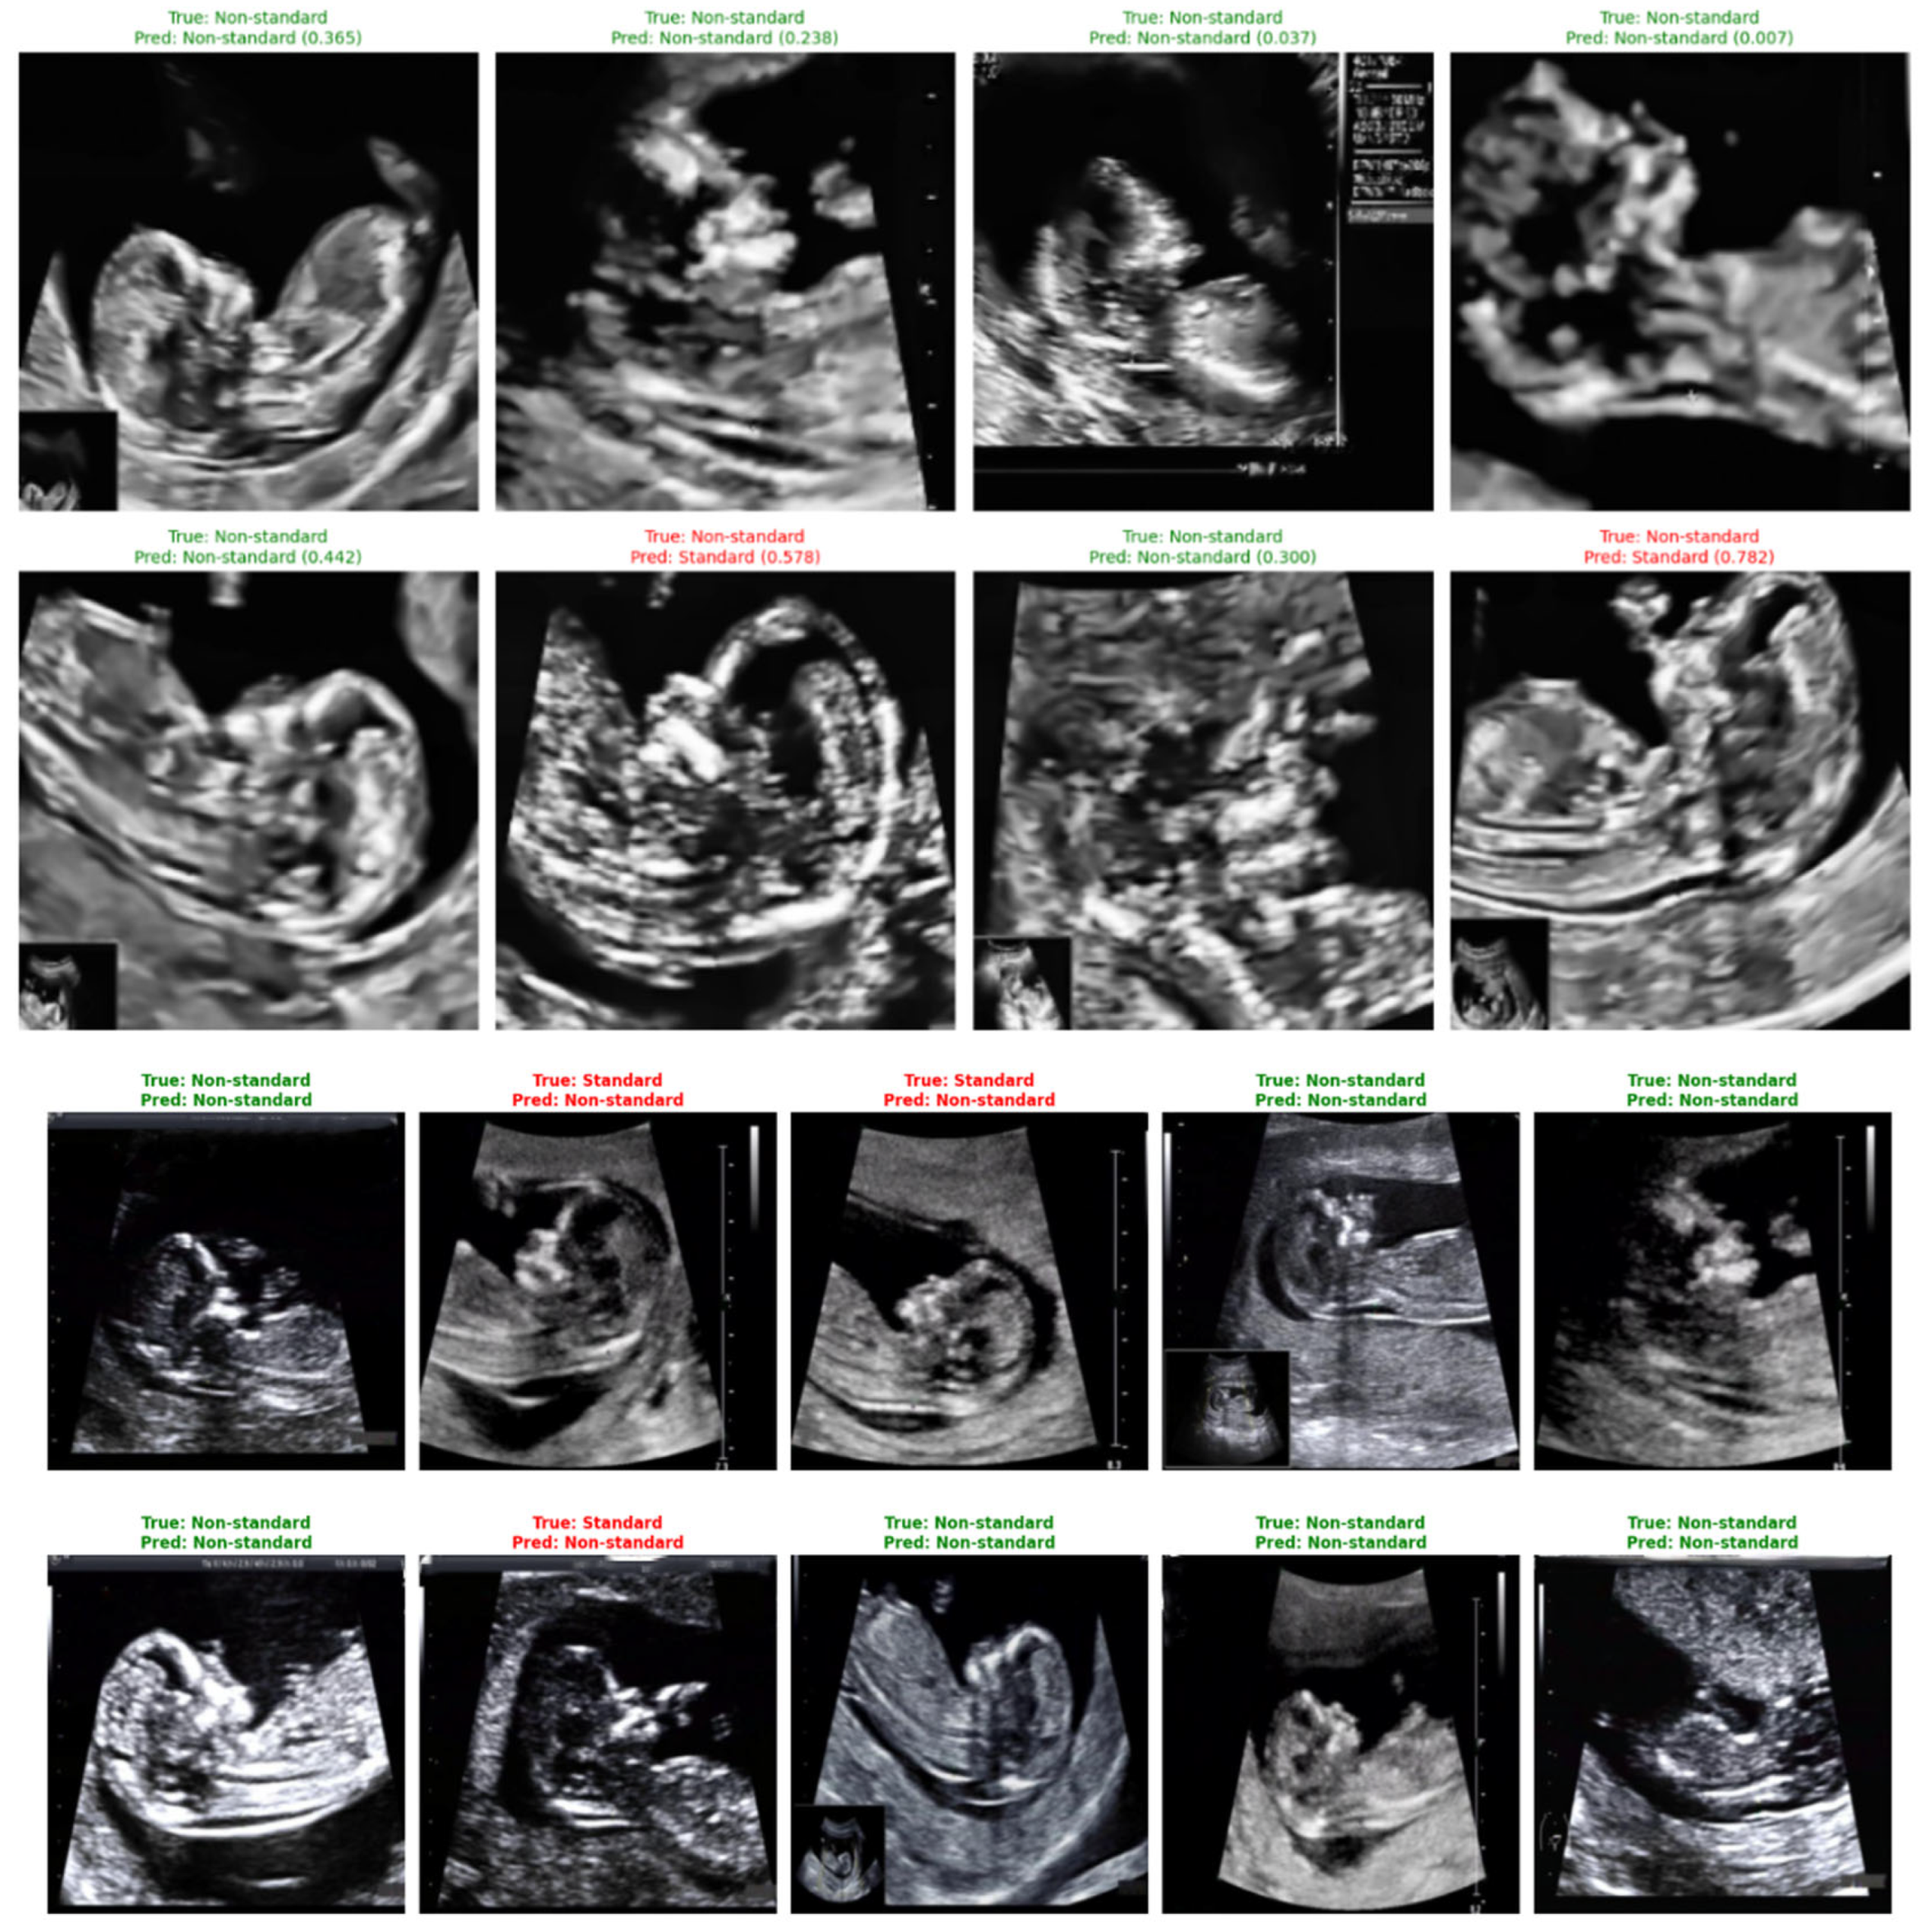

Representative classification outcomes are shown in Figure 24, illustrating both correct and incorrect predictions. Each example includes the ground-truth label, the model’s predicted label, and the associated confidence score.

Figure 24.

Sample predictions of non-standard ultrasound images using DenseNet121.

Correct predictions (shown in green) display high certainty, such as a standard plane identified with a confidence of 0.999. Misclassified cases (shown in red) typically correspond to borderline-quality images containing subtle artifacts, incomplete fetal profiles, or shadowing. These images highlight the nuanced nature of NT plane assessment and help contextualize the few observed errors.